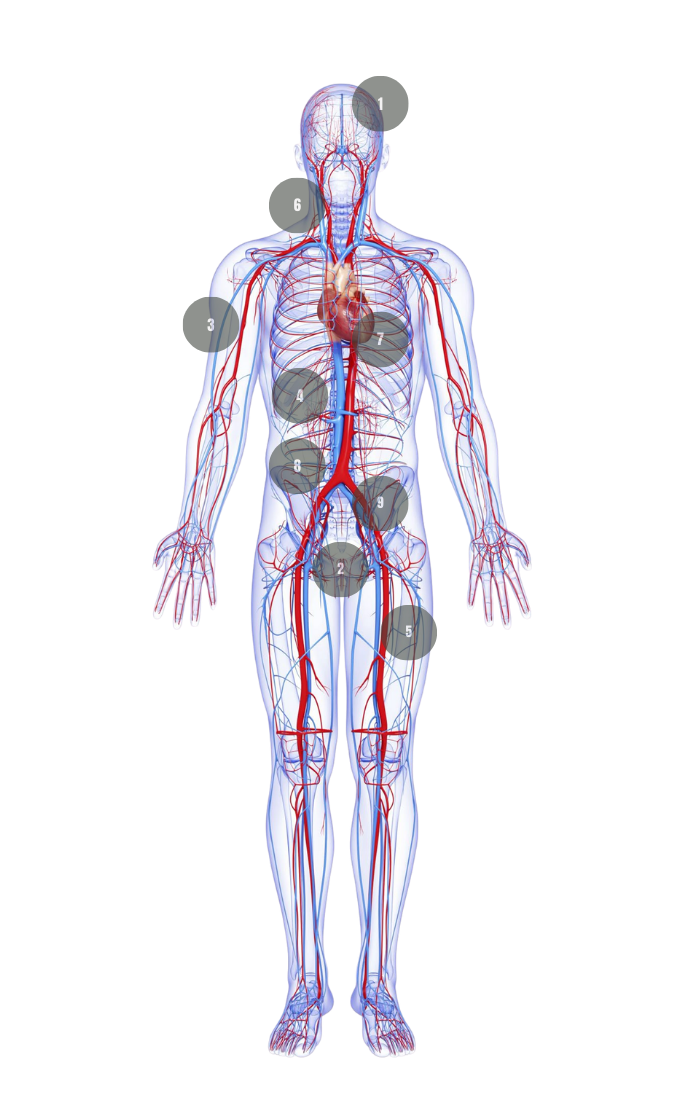

KEY CAUSES:

Testosterone deficiency is the most common contributor. Other causes include aging, heart disease, diabetes, and mental health disorders.

THE IMPORTANCE OF RESTORING TESTOSTERONE

A personalized health transformation that targets hormones and metabolism at the core, combining expert fertility care and TRT optimization to enhance performance, restore balance, and support lasting well-being.